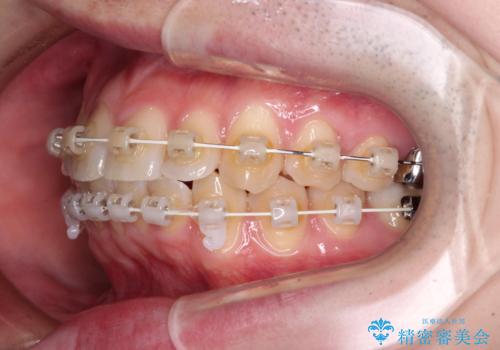

- 上下前歯のデコボコを気にして来院された患者様です。

マウスピース矯正でもワイヤー矯正でも対応可能でしたが、インビザラインによる自己管理が煩わしいとのことで、ワイヤー装置にて矯正治療を行うこととしました。

口元はやや突出感がありましたが抜歯矯正をするほどではないため、舌突出癖を改善するトレーニングをしっかりと行っていただき、現在よりも唇が閉じやすい位置に仕上げていくこととしました。

下顎前歯が思っていた以上に動きが悪く、想定よりも期間がかかってしまいました。

矯正治療後には気になっていた銀歯をセラミックで自然な色に仕上げました。